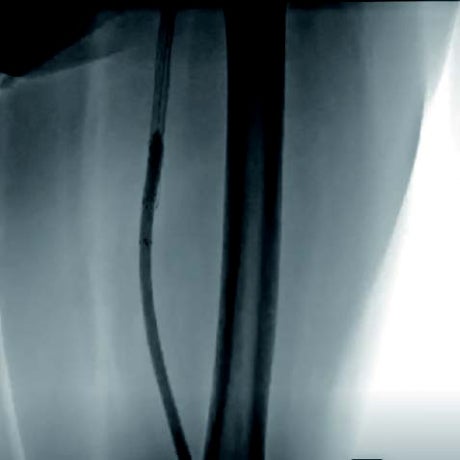

本症例は、初回治療2年後フォローアップ時のエコー所見から、DESの中枢および末梢の病変が閉塞の原因となった可能性が高い。同部位はDCBおよびDESで治療されているにもかかわらず、2年で再狭窄を呈していることから、drug technologyを用いたバルーンおよびステントでの治療は許容できないと判断した。BMI 31.9の肥満であったため右総大腿動脈より対側山越アプローチとした。6 Fr 45 cmガイディングシース + 5.5 Frシースバックアップ下に血管内超音波(IVUS)ガイドで臨んだ。エコー所見どおりDESの中枢および末梢病変は非常に強固であったため、ガイドワイヤー(40 g)で通過した。DES内の病変は非常に柔らかく、ガイドワイヤー(1 g)で通過、DCBのステント内閉塞はガイドワイヤー(15 g)を用い、IVUS下に確実に真腔内で通過した。0.014 inchガイドワイヤーの場合、ガイドワイヤーはステントストラットを容易に通過する。そのため、複数方向からの透視やIVUSを用いることで、確実にステント内を通過していることを確認することが必要となる。また、ステント内はhealthy landingではないことから、確実に前回のステントを最低1 cm以上越えて留置すべきである。DESの再狭窄は、culprit以外が柔らかい赤色血栓であることが多く、この症例もガイドワイヤーの感覚から同様の所見が疑われた。末梢塞栓予防に造影カテーテルによる可及的血栓吸引を行い、バルーン4.0 mm × 300 mmで前拡張をした。末梢病変はバイアバーン® ステントグラフト6 mm × 150 mmを留置、中枢は左浅大腿動脈起始部から10 mmのhealthy landingが残存していたため、同部位よりステントグラフト6 mm × 150 mmを留置した(図1)。高耐圧バルーン6.0 mm × 150 mmで後拡張を行い(図2、図3)、十分にgainを確保し良好なflowで終了した。治療時間は40分、造影剤使用量は70 mL であった。